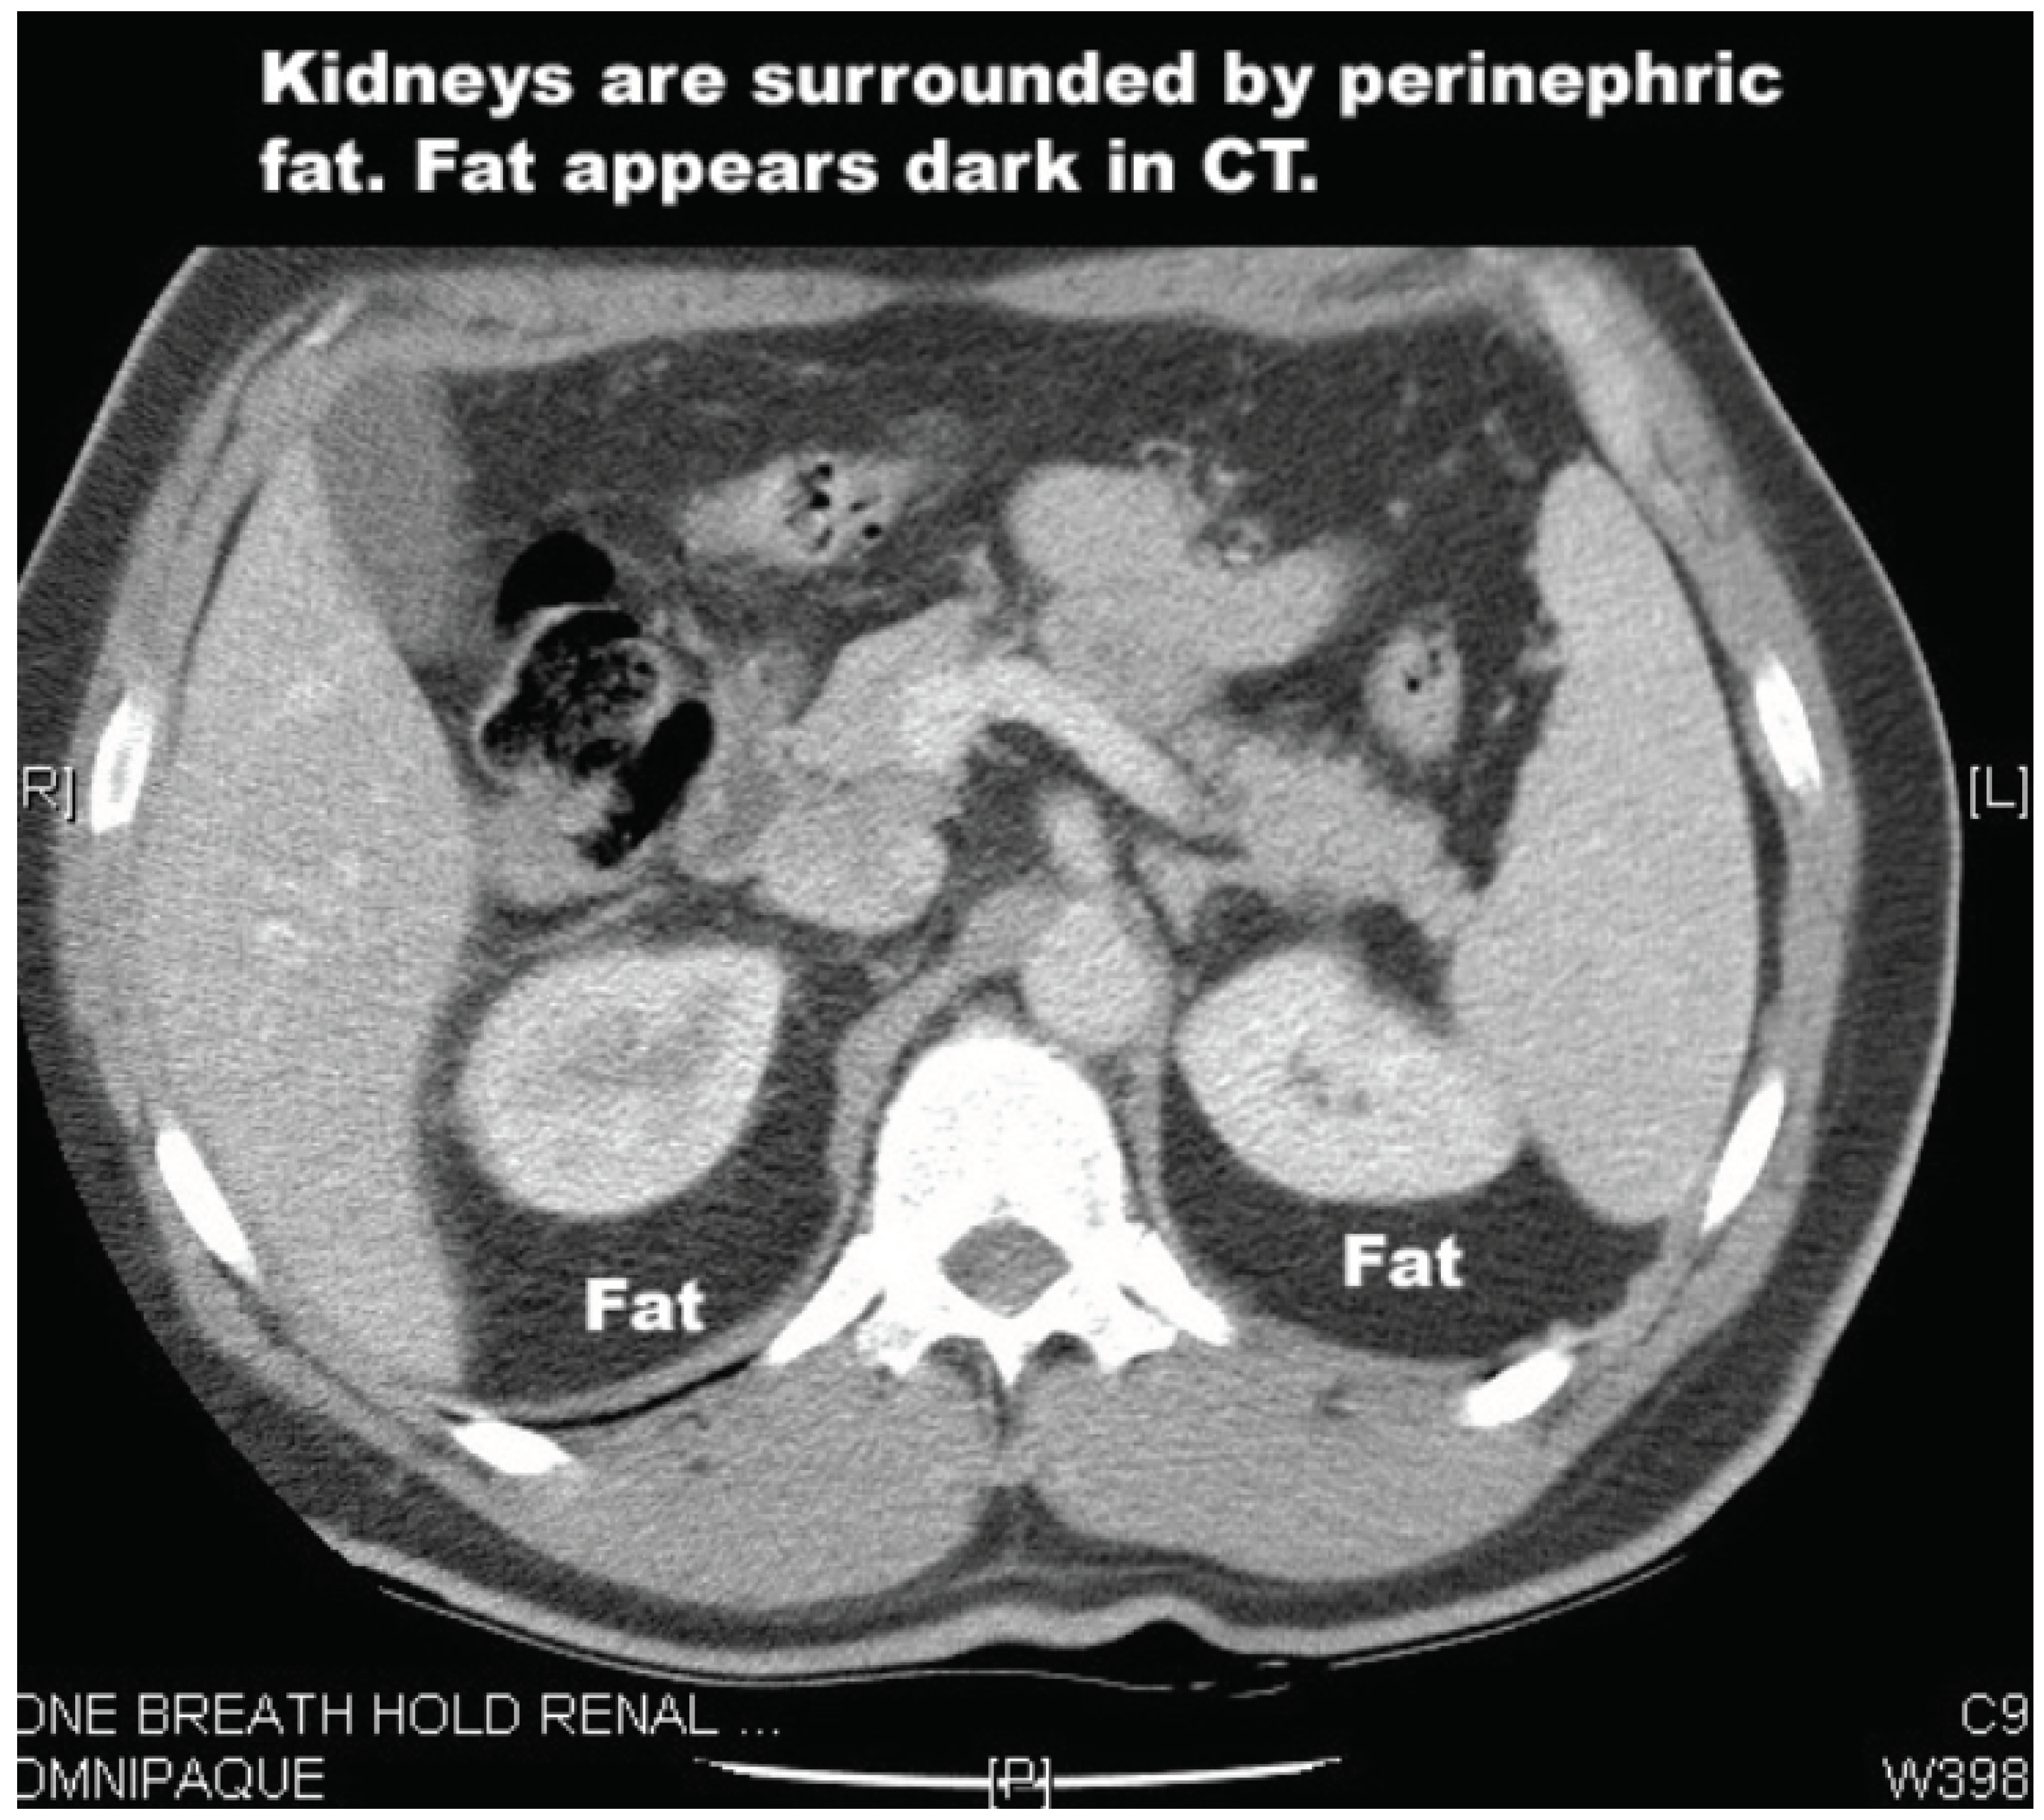

Renal tumours are a potentially challenging target for HIFU given the dense layers of perinephric fat that surround the kidneys. These layers absorb some of the energy of the HIFU beam. A 2020 study investigated this issue to determine the percentage drop of HIFU energy compared to the depth of the perinephric fat [18]. The reduction was significant: from 58% of the output energy level at 2cm deep, to 26% at 5cm. To compensate for this, higher output energies are required, but this increases risk of surrounding tissue damage. However, transplanted kidneys have had their perinephric fat removed, and so transplant patients are perhaps better candidates for HIFU treatment.

Figure 2. CT scan showing perinephric fat.